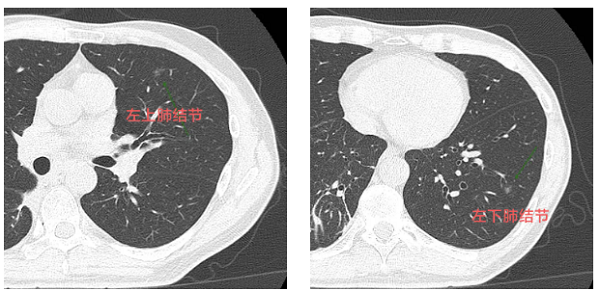

原来,韦先生在每年的例行检查中,发现了双肺多个高危磨玻璃结节,柳州市人民医院健康管理中心立即给韦先生安排了院内就诊。完成第一阶段右肺治疗后,左肺的两枚高危结节亟待解决。

韦先生的“扫雷”行动需要制定一份详细的“作战计划。医院胸外科主任曹健斌主任医师带领多学科诊疗(MDT)团队进行了深入评估。胸外科、肿瘤内科、医学影像科、麻醉科专家为患者制定了“一站式”杂交手术方案通过一次手术,同时处理肺部深处和浅表的多发结节,尽可能保留健康的肺组织,帮助患者术后更快康复